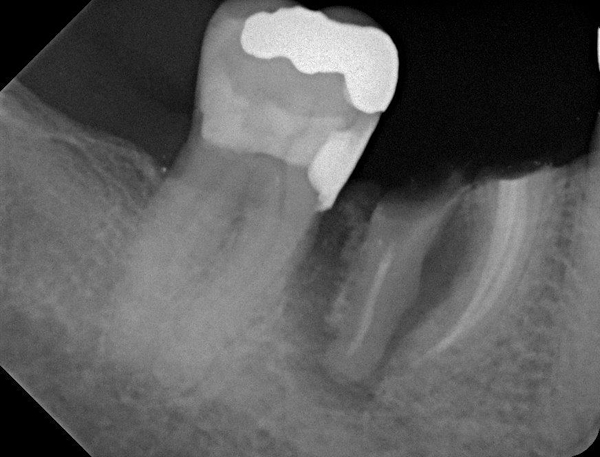

Fig 15. (Case 3) Radiograph of tooth No. 19, which had a hopeless prognosis.

Figure 15

Fig 16. Radiograph of extraction socket. Buccal and lingual plates were defective.

Figure 16